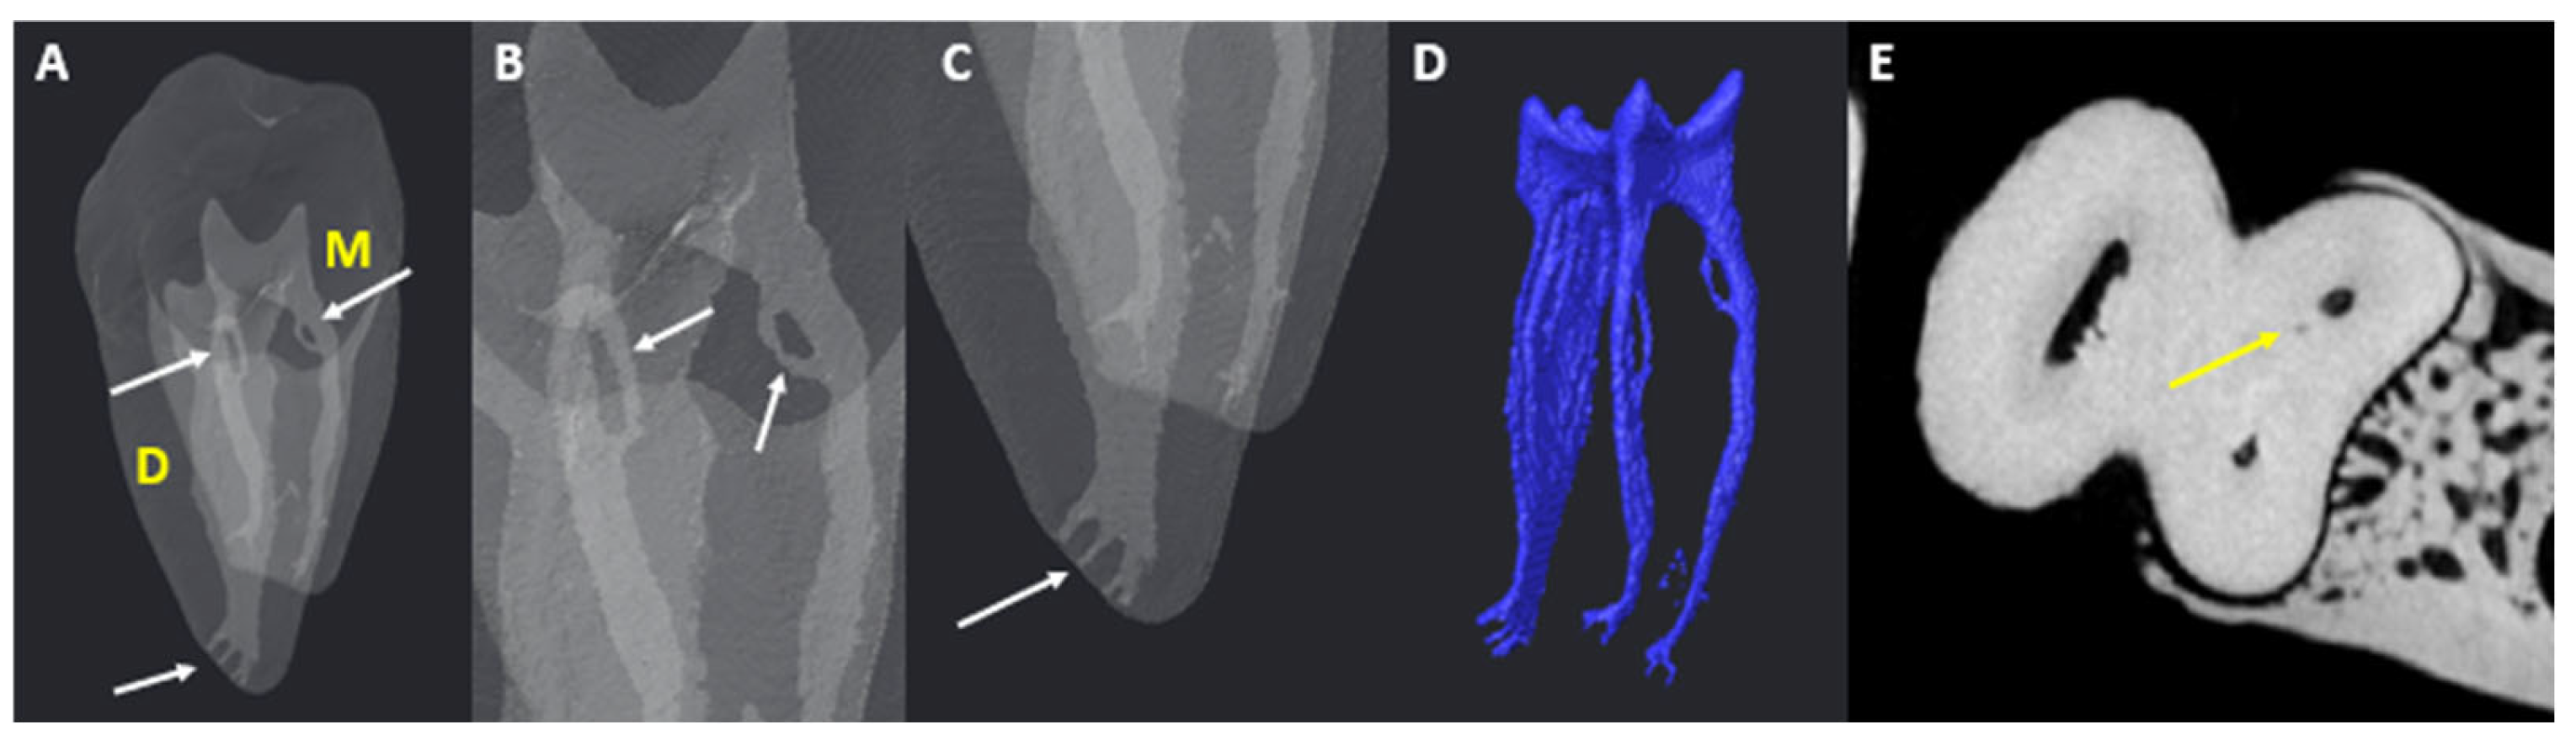

3.3. Number of Canals per Root

3.4. Chamber Canals

3.5. Accessory Canals (ACs)

3.5.1. M Root

3.5.2. D Root